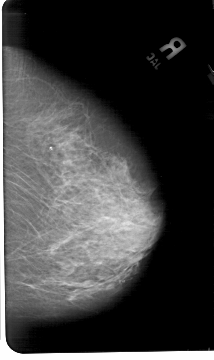

A_1496_1.LEFT_CC

LEFT_CC LINES 5491 PIXELS_PER_LINE 3571 BITS_PER_PIXEL 12 RESOLUTION 43.5 OVERLAY

FILE: A_1496_1.LEFT_CC.OVERLAY

TOTAL_ABNORMALITIES 1

ABNORMALITY 1

LESION_TYPE CALCIFICATION TYPE AMORPHOUS DISTRIBUTION CLUSTERED

ASSESSMENT 2

SUBTLETY 5

PATHOLOGY BENIGN

TOTAL_OUTLINES 1